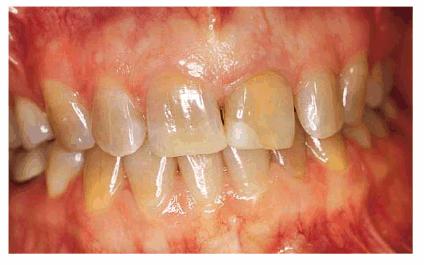

Some examples of these different discolorations can be seen in Figures 16-2A

and B 16-8A and B 16-11A and B 16-12A and B, and ,. Additionally, the discoloration

can either be of a generalized nature or specific to one tooth or one location

Figure 16-2A and B: Total neglect resulted in severe staining

of this patient's teeth.